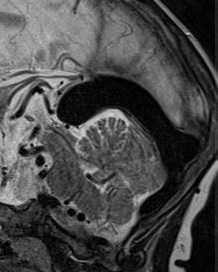

При МРТ головного мозга на аксиальных МРТ любого типа выявляется округлое образование с отсутствием сигнала в области пластины четверохолмия. На сагиттальных МРТ головного мозга отчетливо видно расширение и отсутствин сигнала от расширенной медианной прозэнцефалической вены, а также часто от прямого синуса и синуса намета. При МРА видна расширенная артерия. Тромбированные участки мальформации дают повышенный сигнал на МРТ головного мозга любого типа. На КТ видно скопление контраста в расширенной вене. Ангиография позволяет разделить АВГ на 4 типа в зависимости от питающей артерии.

МРТ головного мозга. Т2-взвешенная сагиттальная МРТ. Аневризма вены Галена.